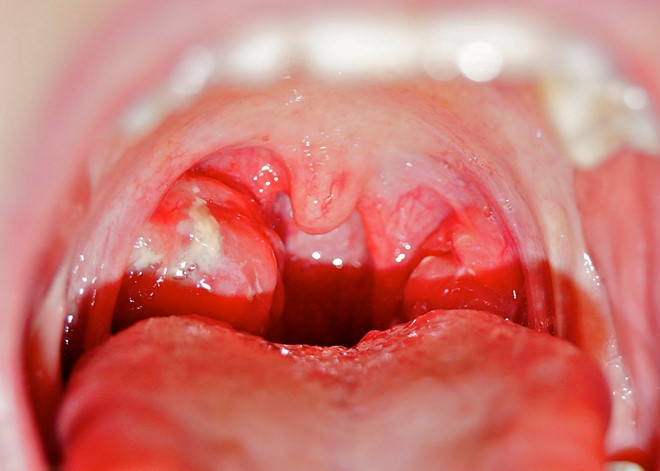

04/12/2017 16:41Dấu hiệu không được chủ quan khi trẻ bị viêm mũi họng

Bác sĩ Nguyễn Minh Đức, khoa Tai Mũi Họng, Bệnh viện Việt Pháp, cho biết viêm mũi họng rất dễ xảy ra ở trẻ, đặc biệt vào thời tiết đột ngột thay đổi.

“Viêm mũi họng tưởng chừng dễ nhận biết nhưng các mẹ không được chủ quan vì bệnh có thể gây ra biến chứng nguy hiểm như viêm tai giữa, viêm đường hô hấp dưới như viêm phế quản phổi, viêm phổi, viêm khớp (thấp tim tiến triển), viêm cầu thận cấp nếu tác nhân gây bệnh là vi khuẩn liên cầu nhóm A (S.pyogenes)”, bác sĩ Đức cảnh báo.

Dấu hiệu nhận biết viêm mũi họng

- Chảy nước mũi, ngạt mũi, hắt hơi, đau họng, ho. Lúc đầu ho khan, sau ho có đờm.

- Sốt nhẹ hoặc sốt cao có thể lên đến 39-40 độ C

- Trẻ quấy khóc, biếng ăn, khó ngủ và thường thở bằng miệng do ngạt mũi. Trẻ có thể thở nhanh hơn bình thường, đôi khi co rút lồng ngực (hay gặp ở trẻ nhỏ, lúc đó có thể tình trạng viêm đã lan xuống đường hô hấp dưới)

- Nôn, đi ngoài phân lỏng

Dấu hiệu cần đi khám

Bác sĩ Đức cũng cảnh báo khi trẻ có một trong các biểu hiện sau, cần đưa trẻ bị viêm mũi họng cấp đi khám ngay:

- Sốt cao liên tục dùng thuốc và chườm ấm không hạ sốt

- Trẻ ho nhiều, thở nhanh, khó thở

- Trẻ nôn nhiều, đi ngoài phân lỏng nhiều lần trong ngày

- Chảy mủ tai

- Không tốt lên sau 2 ngày điều trị